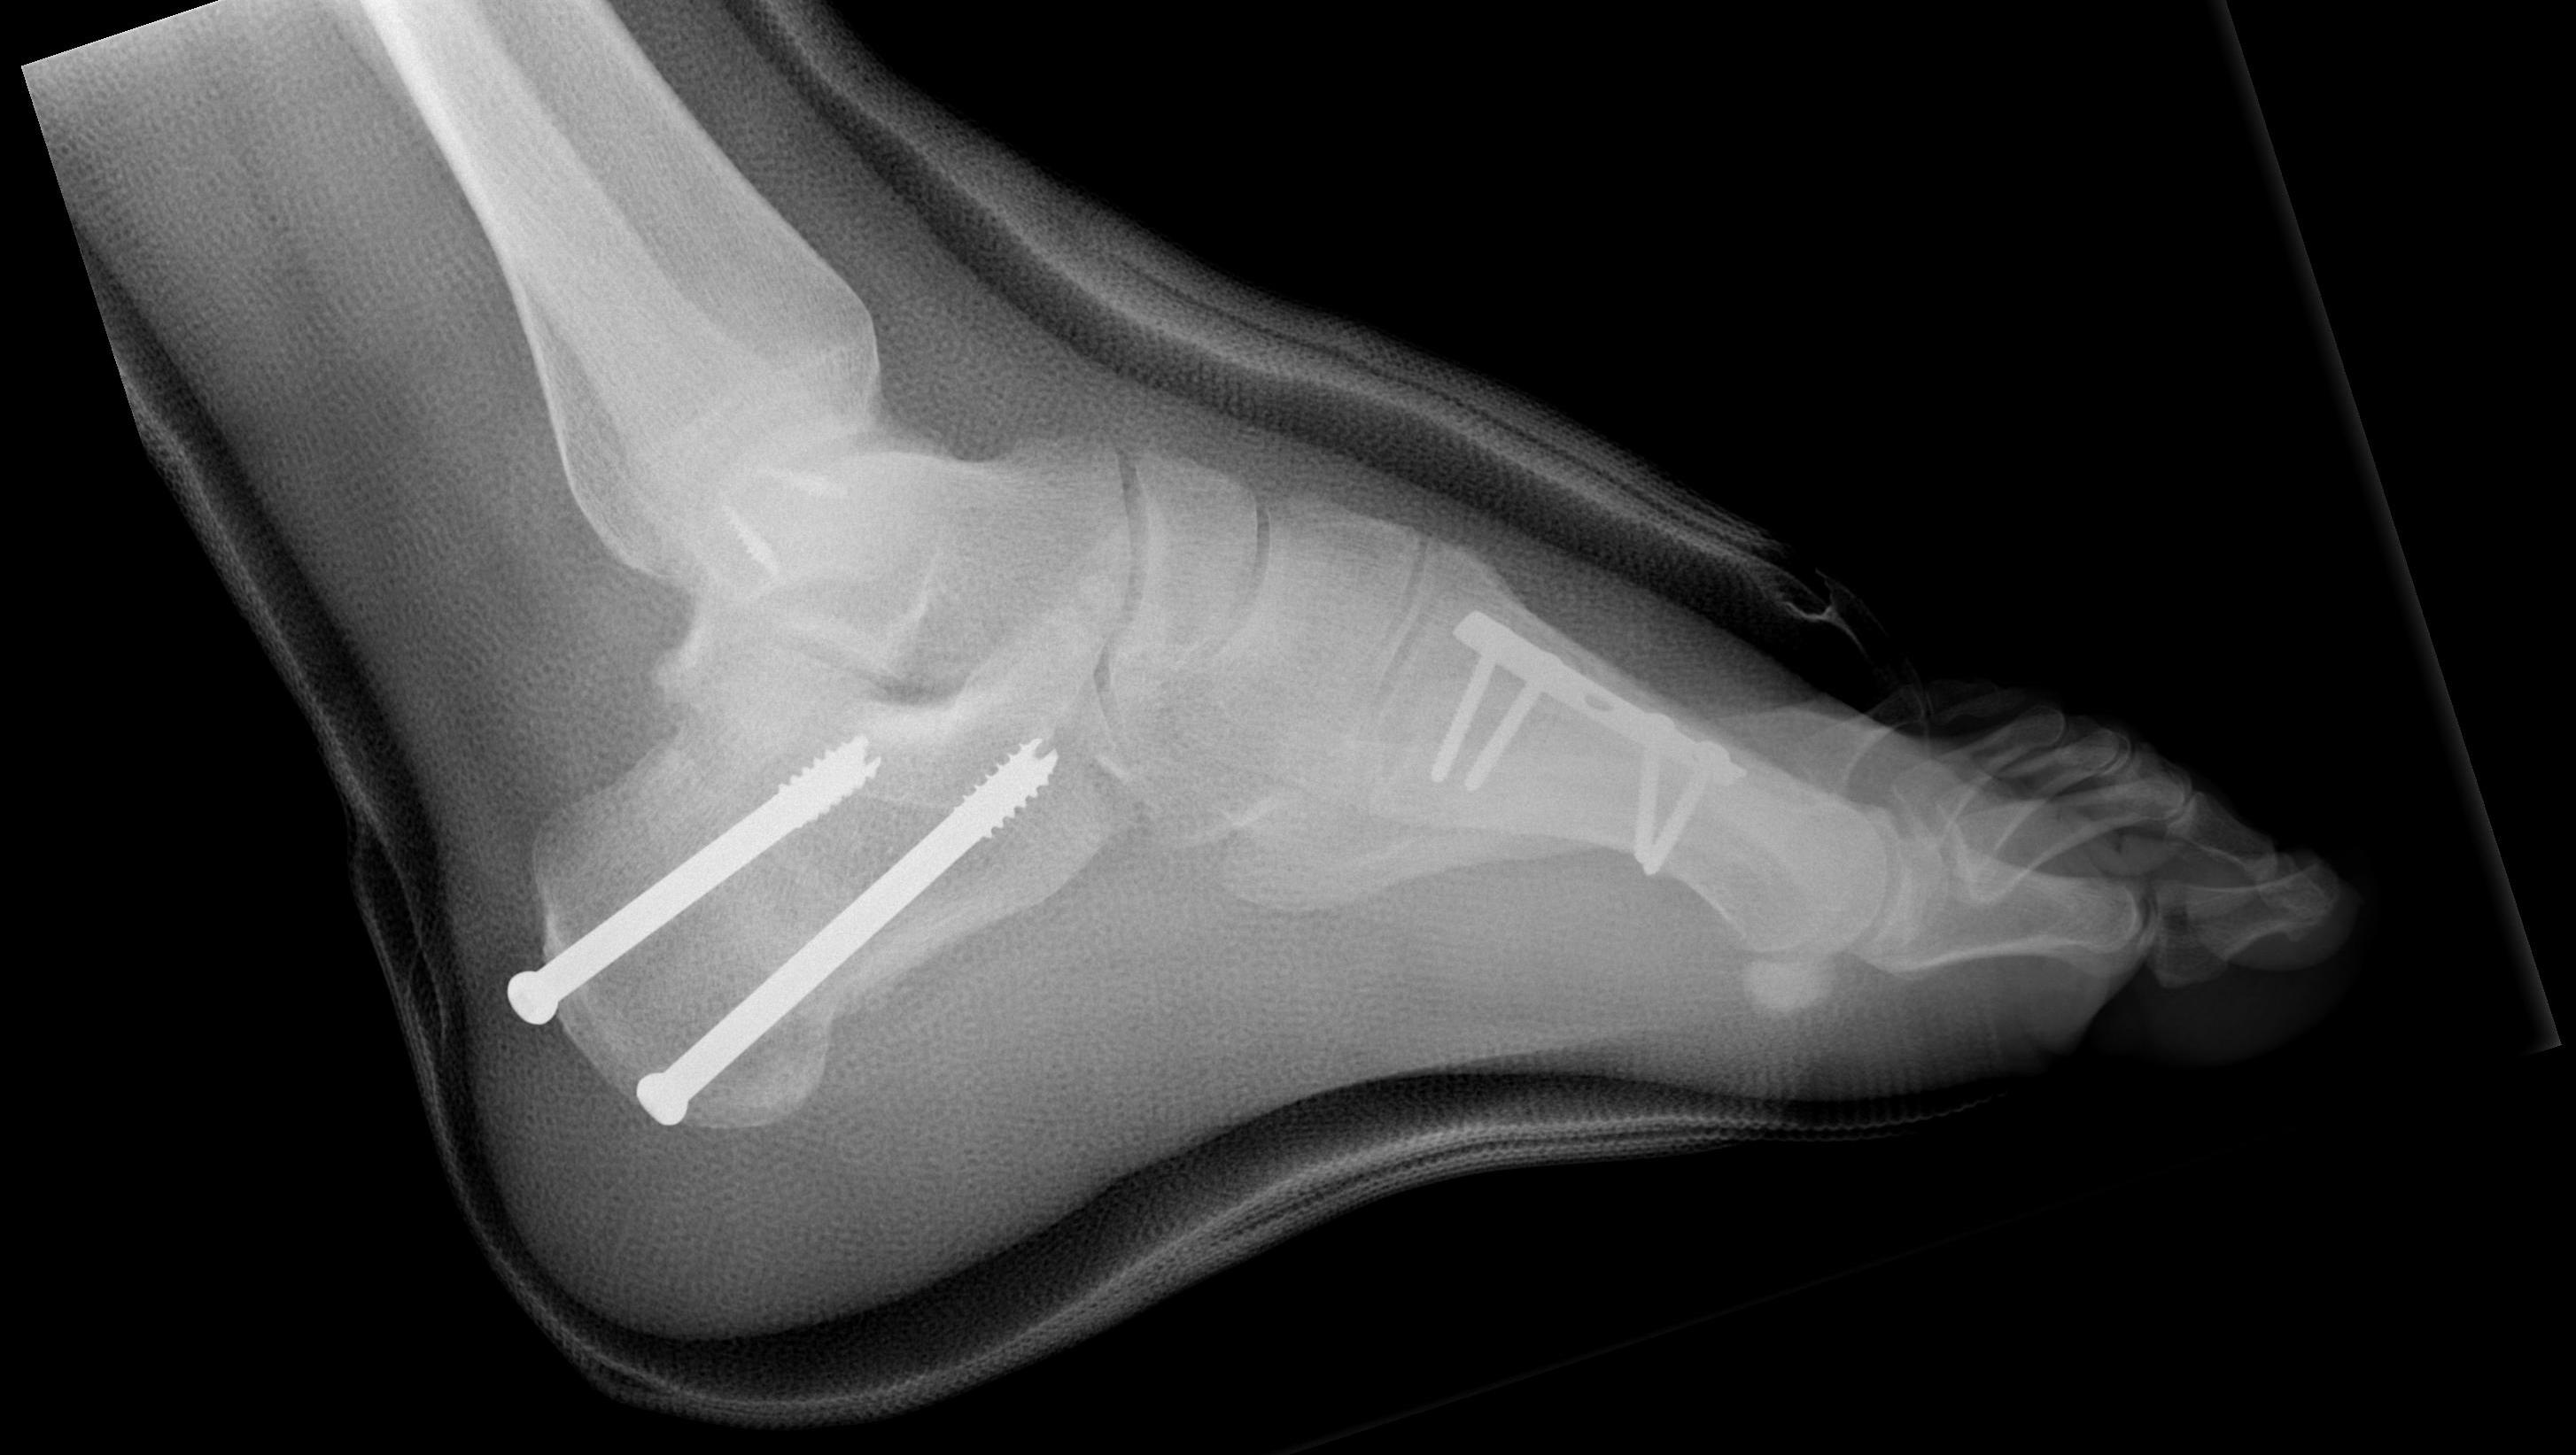

Triple Arthrodesis

Meary closing wedge tarsectomy

Indication

Fixed deformity, difficult cases

Results

Simon et al Foot Ankle Surg 2019

- tarsectomy / calcaneal osteotomy / metatarsal osteotomy in 26 feet

- good results 58%

- fair results 23%

- poor results 19%